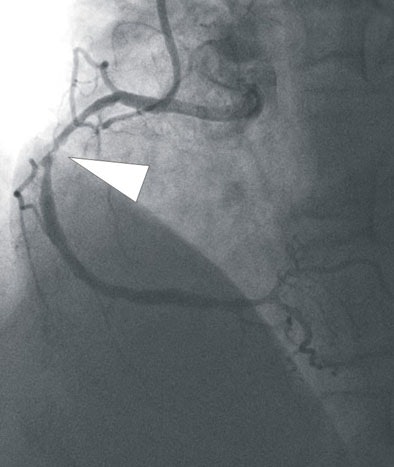

| In a 64-year-old man presenting with chest pain, 3D and multiplanar reconstructions of coronary CTA images show a significant stenosis in the first diagonal branch of the left anterior descending (LAD) artery and a 70% stenosis in the mid right circumflex artery (RCA) (arrows). All images courtesy of Dr. Balázs Ruzsics, Ph.D., and Dr. U. Joseph Schoepf. |

| In a 64-year-old man with chest pain, conventional catheter angiography confirmed the coronary CTA findings, and described a 50% ostial stenosis with diffuse disease throughout the vessel and a discrete 90% stenosis in the mid right circumflex artery (RCA) (arrows). |